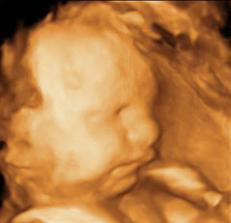

Buduci rodicia 🙂

Nase dlho ocakavane tehu sa uspesne skoncilo a zacina nova uzasna, krasna, neuveritelna etapa menom Tomasko. 🙂